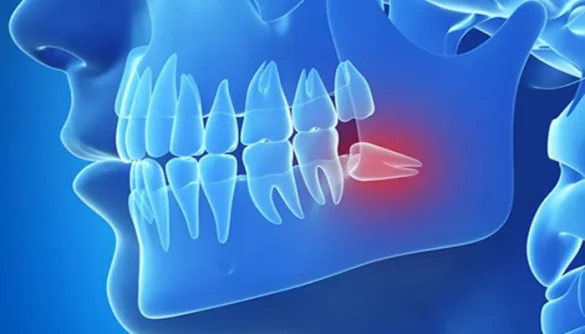

Impaction: Wisdom teeth can become impacted when there is not enough space in the jaw for them to fully emerge. This can cause pain as the tooth pushes against other teeth or the surrounding gum tissue.

Pressure on Neighboring Teeth: Wisdom teeth pushing against adjacent teeth can cause discomfort, especially if the teeth are already crowded or misaligned.